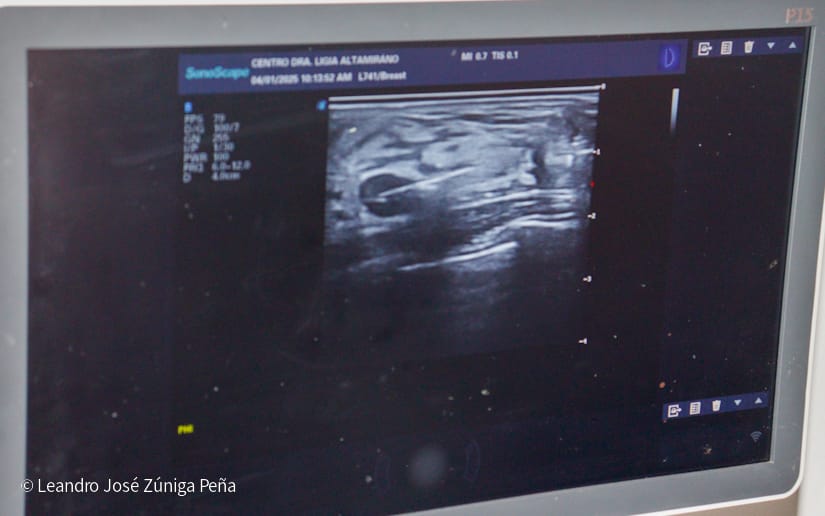

La doctora Carmen Cruz, directora del Hospital, explicó cómo se lleva a cabo el procedimiento: "Esta biopsia se realiza tomando tejido de la imagen sospechosa que ha sido previamente detectada en un ultrasonido. Junto al médico que asiste en el proceso, se procede a extraer tejido de la zona donde se encuentra una lesión que podría indicar alguna alteración", señaló.